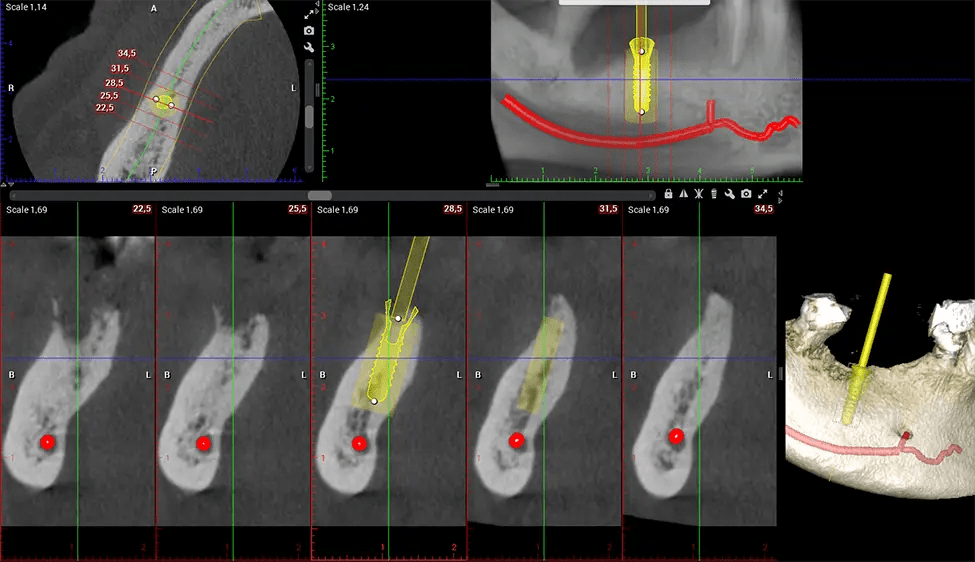

Cuando se combina con extracciones, colocación de implantes dentales o injertos óseos, la tecnología CBCT puede brindarle una experiencia más rápida y mucho más cómoda. Esto se debe a que la imagen 3D proporciona una imagen más detallada de toda su cavidad bucal, lo que le permite a su dentista guiarlo en cada paso del proceso antes de que ocurra. Esto a menudo ayuda a los pacientes a sentirse más preparados y cómodos en general, especialmente si han tenido una experiencia traumática con tratamientos dentales anteriores.

Después del proceso de escaneo, las imágenes de rayos X capturadas son procesadas por el software CBCT, que aplica algoritmos para reconstruir una imagen 3D detallada del área escaneada. El software recopila estas imágenes de rayos X individuales y crea una representación digital en 3D de la anatomía del paciente. El dentista o el radiólogo pueden ver y analizar la imagen CBCT 3D reconstruida. Esta imagen se puede manipular, rotar y acercar o alejar para examinar estructuras específicas y evaluar la condición del paciente.

Planmeca Viso G7 CBCT (Cone Beam CT Scan) está diseñado para superar las demandas de los líderes de la industria, los especialistas y las grandes instituciones. Tiene un gran sensor de ø25×30 cm con cuatro cámaras integradas. Puede capturar tamaños de volumen ilimitados, desde ø3×3 cm hasta ø30x30cm, capturando el casquete escutelario a través de C7 en la columna cervical. Planmeca Viso G7 ofrece el escaneo de volumen único más grande de la industria de ø30×19 cm. Está preparado para manejar modalidades de imágenes avanzadas como la tecnología Planmeca ProFace® y Planmeca 4D™ Jaw Motion. El soporte occipital para la cabeza permite una visión sin obstáculos del tejido facial.

Nuestra tecnología SCARA patentada permite a los médicos capturar verdaderas alas de mordida extraorales que son tan precisas para detectar caries como una serie de alas de mordida 2D, pero con la mitad de la dosis de radiación. Con nuestras alas de mordida, los médicos pueden ver los ápices de los dientes en ambas mandíbulas, lo que proporciona una visión más completa de la anatomía de los pacientes.